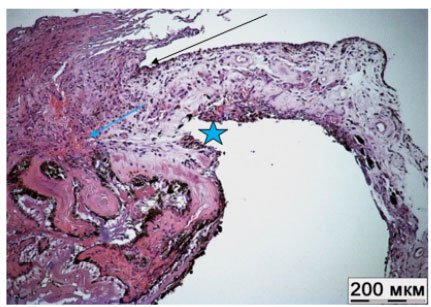

Pathogenetic Classification of Primary Angle-Closure Glaucoma

Bakunina NA and Balashova LM. 14(6): 25-32.